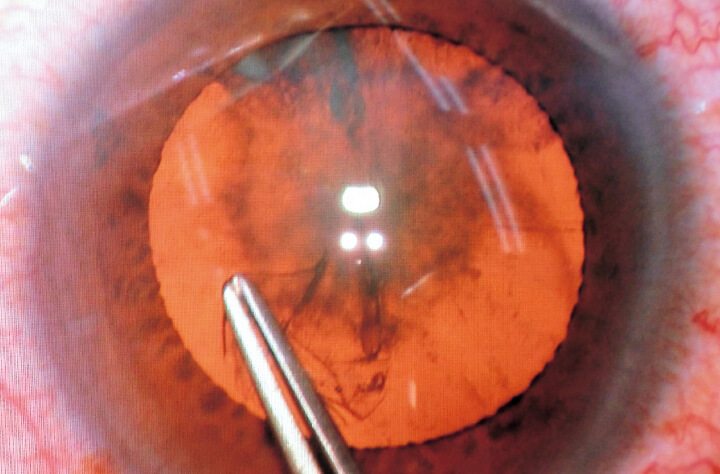

Thanks to the bright red reflex illumination, the red reflex can be seen extremely clearly.

Even during ultrasonic phacoemulsification and aspiration (PEA), which can weaken the red reflex illumination, the lens can be seen clearly due to the bright red reflex illumination.

Sufficient red reflex illumination can also be obtained for small pupils. In addition, bright and stable red reflex illumination can always be obtained, even when the direction of the eye changes.

Using only red reflex illumination produces high contrast, enhanced images of the lens.

Using the main illumination and red reflex illumination simultaneously and controlling their distribution enhances the 3D appearance of the image.